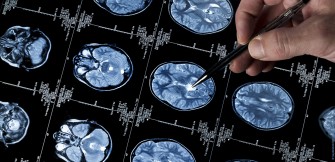

Un "projet de signature neurologique cérébrale", système lisant les signaux diffusés par le cerveau d’un handicapé incapable de parler, a été développé par le chercheur Djamel Bouchefra du centre de d...